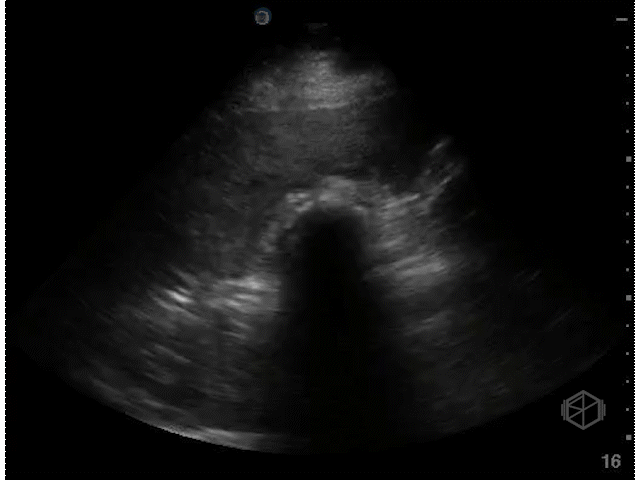

The above clips demonstrate some interesting pathology. There appears to be a hyperechoic flap tethered to the optic nerve. This patient has a retinal detachment. There may also potentially be a vitreous detachment.

• Retinal detachment appears as a thick hyperechoic membrane. It can be tethered to the optic nerve if large, or if smaller (or not close to to the optic nerve), attached to another portion of the posterior wall of the eye. The retinal detachment will move slightly with oculo-kinetics but will remained tethered. POCUS has a high sensitivity and specificity if done correctly for the detection of retinal detachments.